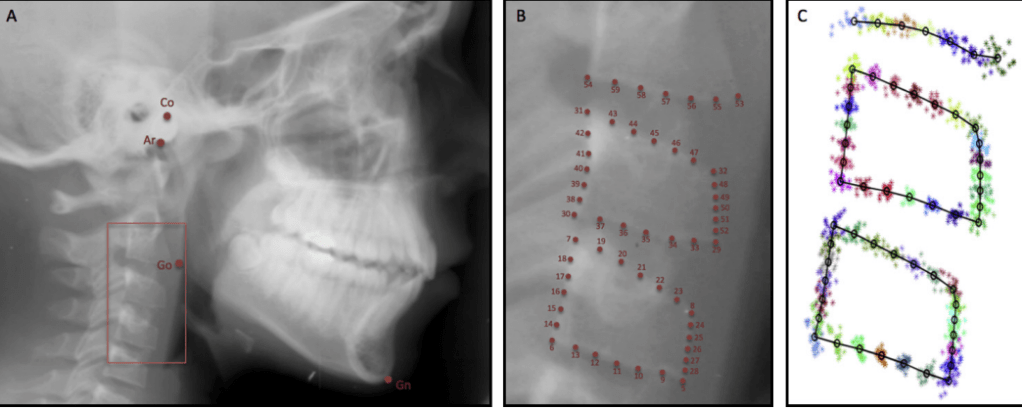

- Pre-check: Lateral ceph or CBCT (especially in thin palates)

Routine lateral cephalogram shows limited palatal height near the first premolar line. What is the most appropriate next diagnostic step before insertion?

C. Request CBCT for precise VBH assessment

Explanation: CBCT provides accurate 3D VBH estimation and should be used when cephalogram suggests borderline bone height.